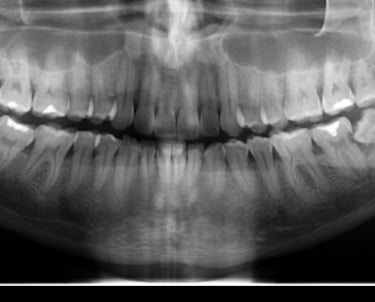

Exame de imagem

Na odontologia, tanto exames de imagem quanto exames laboratoriais, tem papel fundamental para um diagnostico preciso, planejamento adequado e segurança do paciente. Exames de imagem ajudam a ver o que esta escondido e planejar corretamente. Exames laboratoriais trazem segurança, avaliando o paciente como um todo.